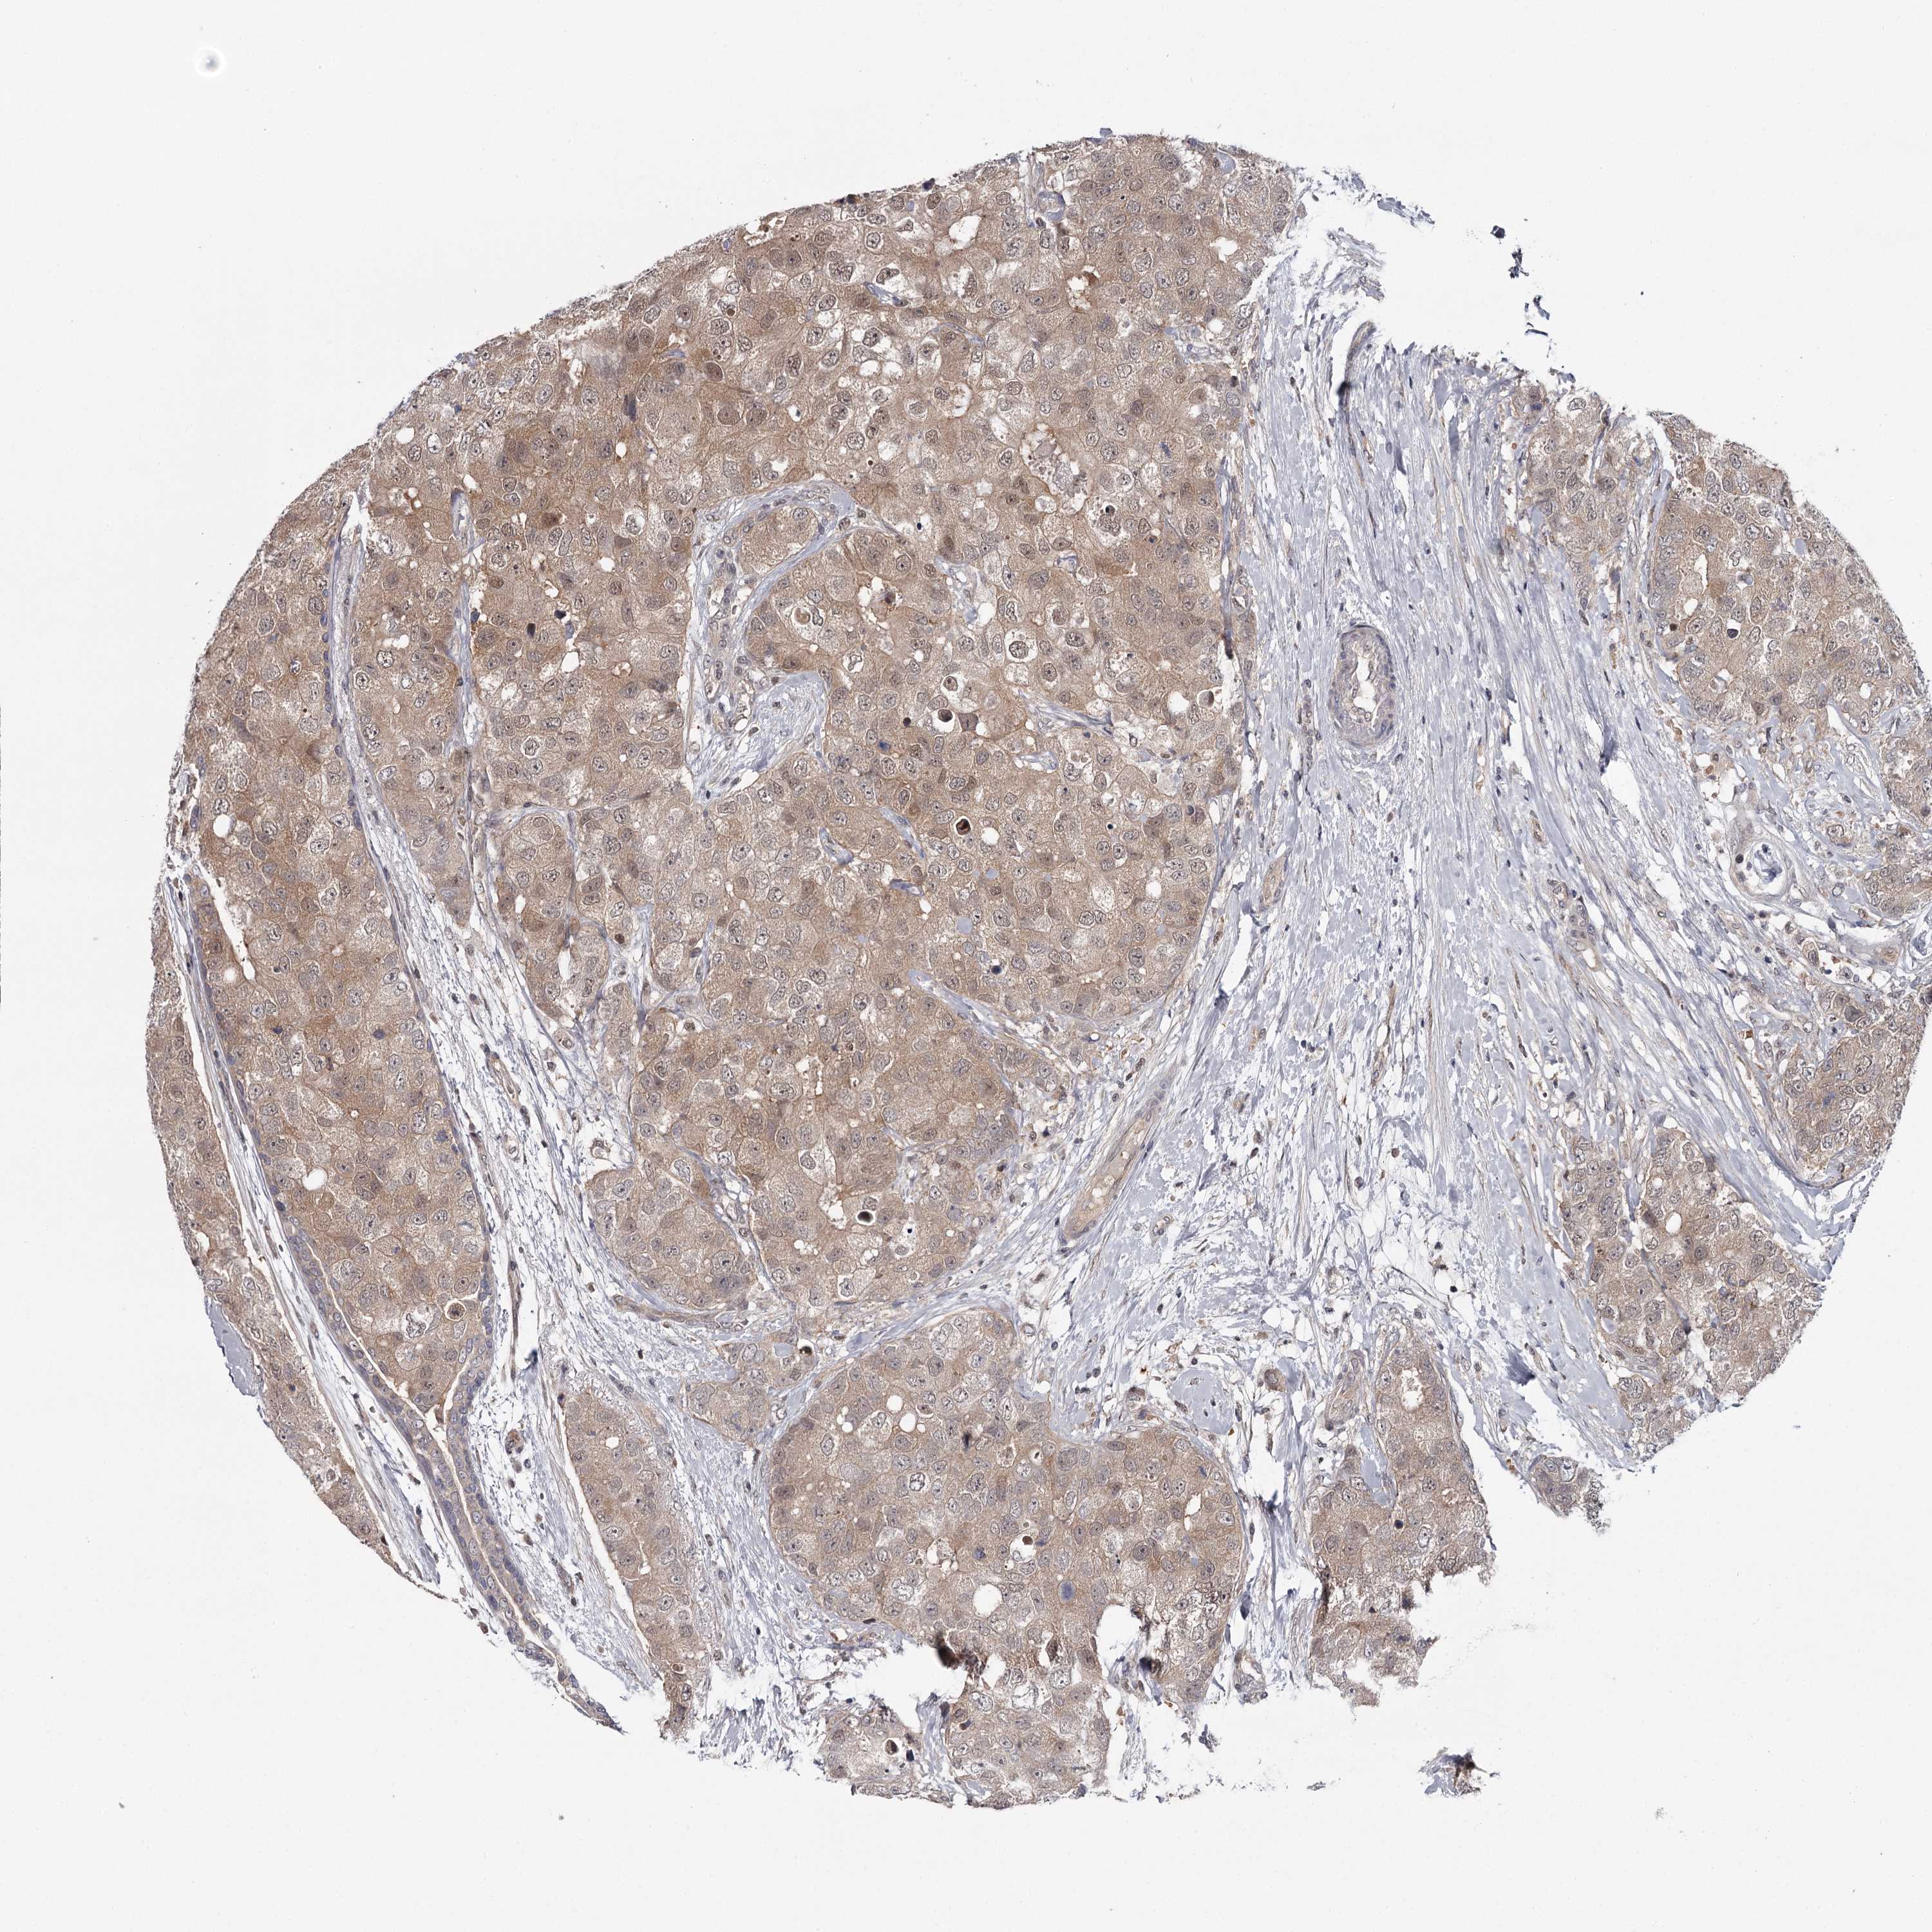

BRCA TCGA BRCA VALIDATION PROTEIN EXPRESSION